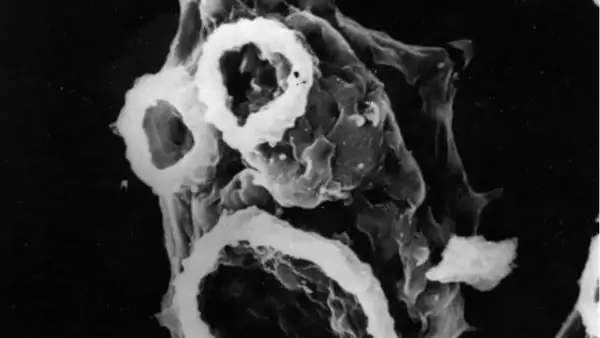

Хотя это очень редкое заболевание во всем мире, его трудно лечить, поедающая мозг амеба (Naegleria fowleri), что обычно приводит к смерти. Паразитарные препараты, применяемые при лечении этих амеб, которые могут передаваться из грязных вод, общественных бассейнов, прудов, в небольшом количестве проходят через гематоэнцефалический барьер. Если увеличить дозу для уничтожения амебы, проявляются побочные действия препарата и отравляют человека. Ученые, ищущие решение этой проблемы, исследовали, могут ли они убить этих амеб с помощью противосудорожных препаратов диазепам, фенобарбитал и фенитоин, которые могут преодолевать гематоэнцефалический барьер. Самым большим преимуществом этих препаратов является то, что они уже одобрены Американским управлением по санитарному надзору за качеством пищевых продуктов и медикаментов (FDA). Из-за его антимикробного свойства ученые добавили наночастицы серебра в лекарства для повышения их эффективности.

В ходе испытаний было замечено, что три препарата могут убить амебу в одиночку, и они более эффективны, если наночастицы серебра добавляются химическим путем. Кроме того, препараты с наночастицами серебра не наносили вреда клеткам человека, а также защищали их от микробов и повышали выживаемость. Установлено, что препараты убивают микробы, связываясь с белковыми сенсорами или ионными каналами в мембране амебы.